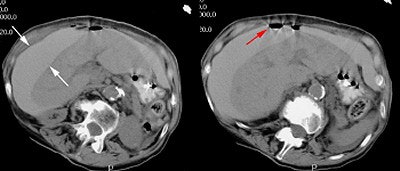

![]() |

| CT scan from a patient with a perforated gastric ulcer. The patient presented with severe abdominal pain. Oral contrast given prior to the exam can be seen free within the peritoneal cavity about the liver (white arrows). There is also free air (red arrow). The findings are consistent with a perforated viscus. |